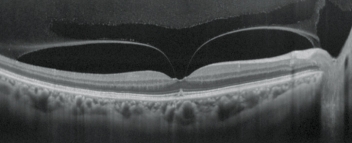

青光眼分析

青光眼進程